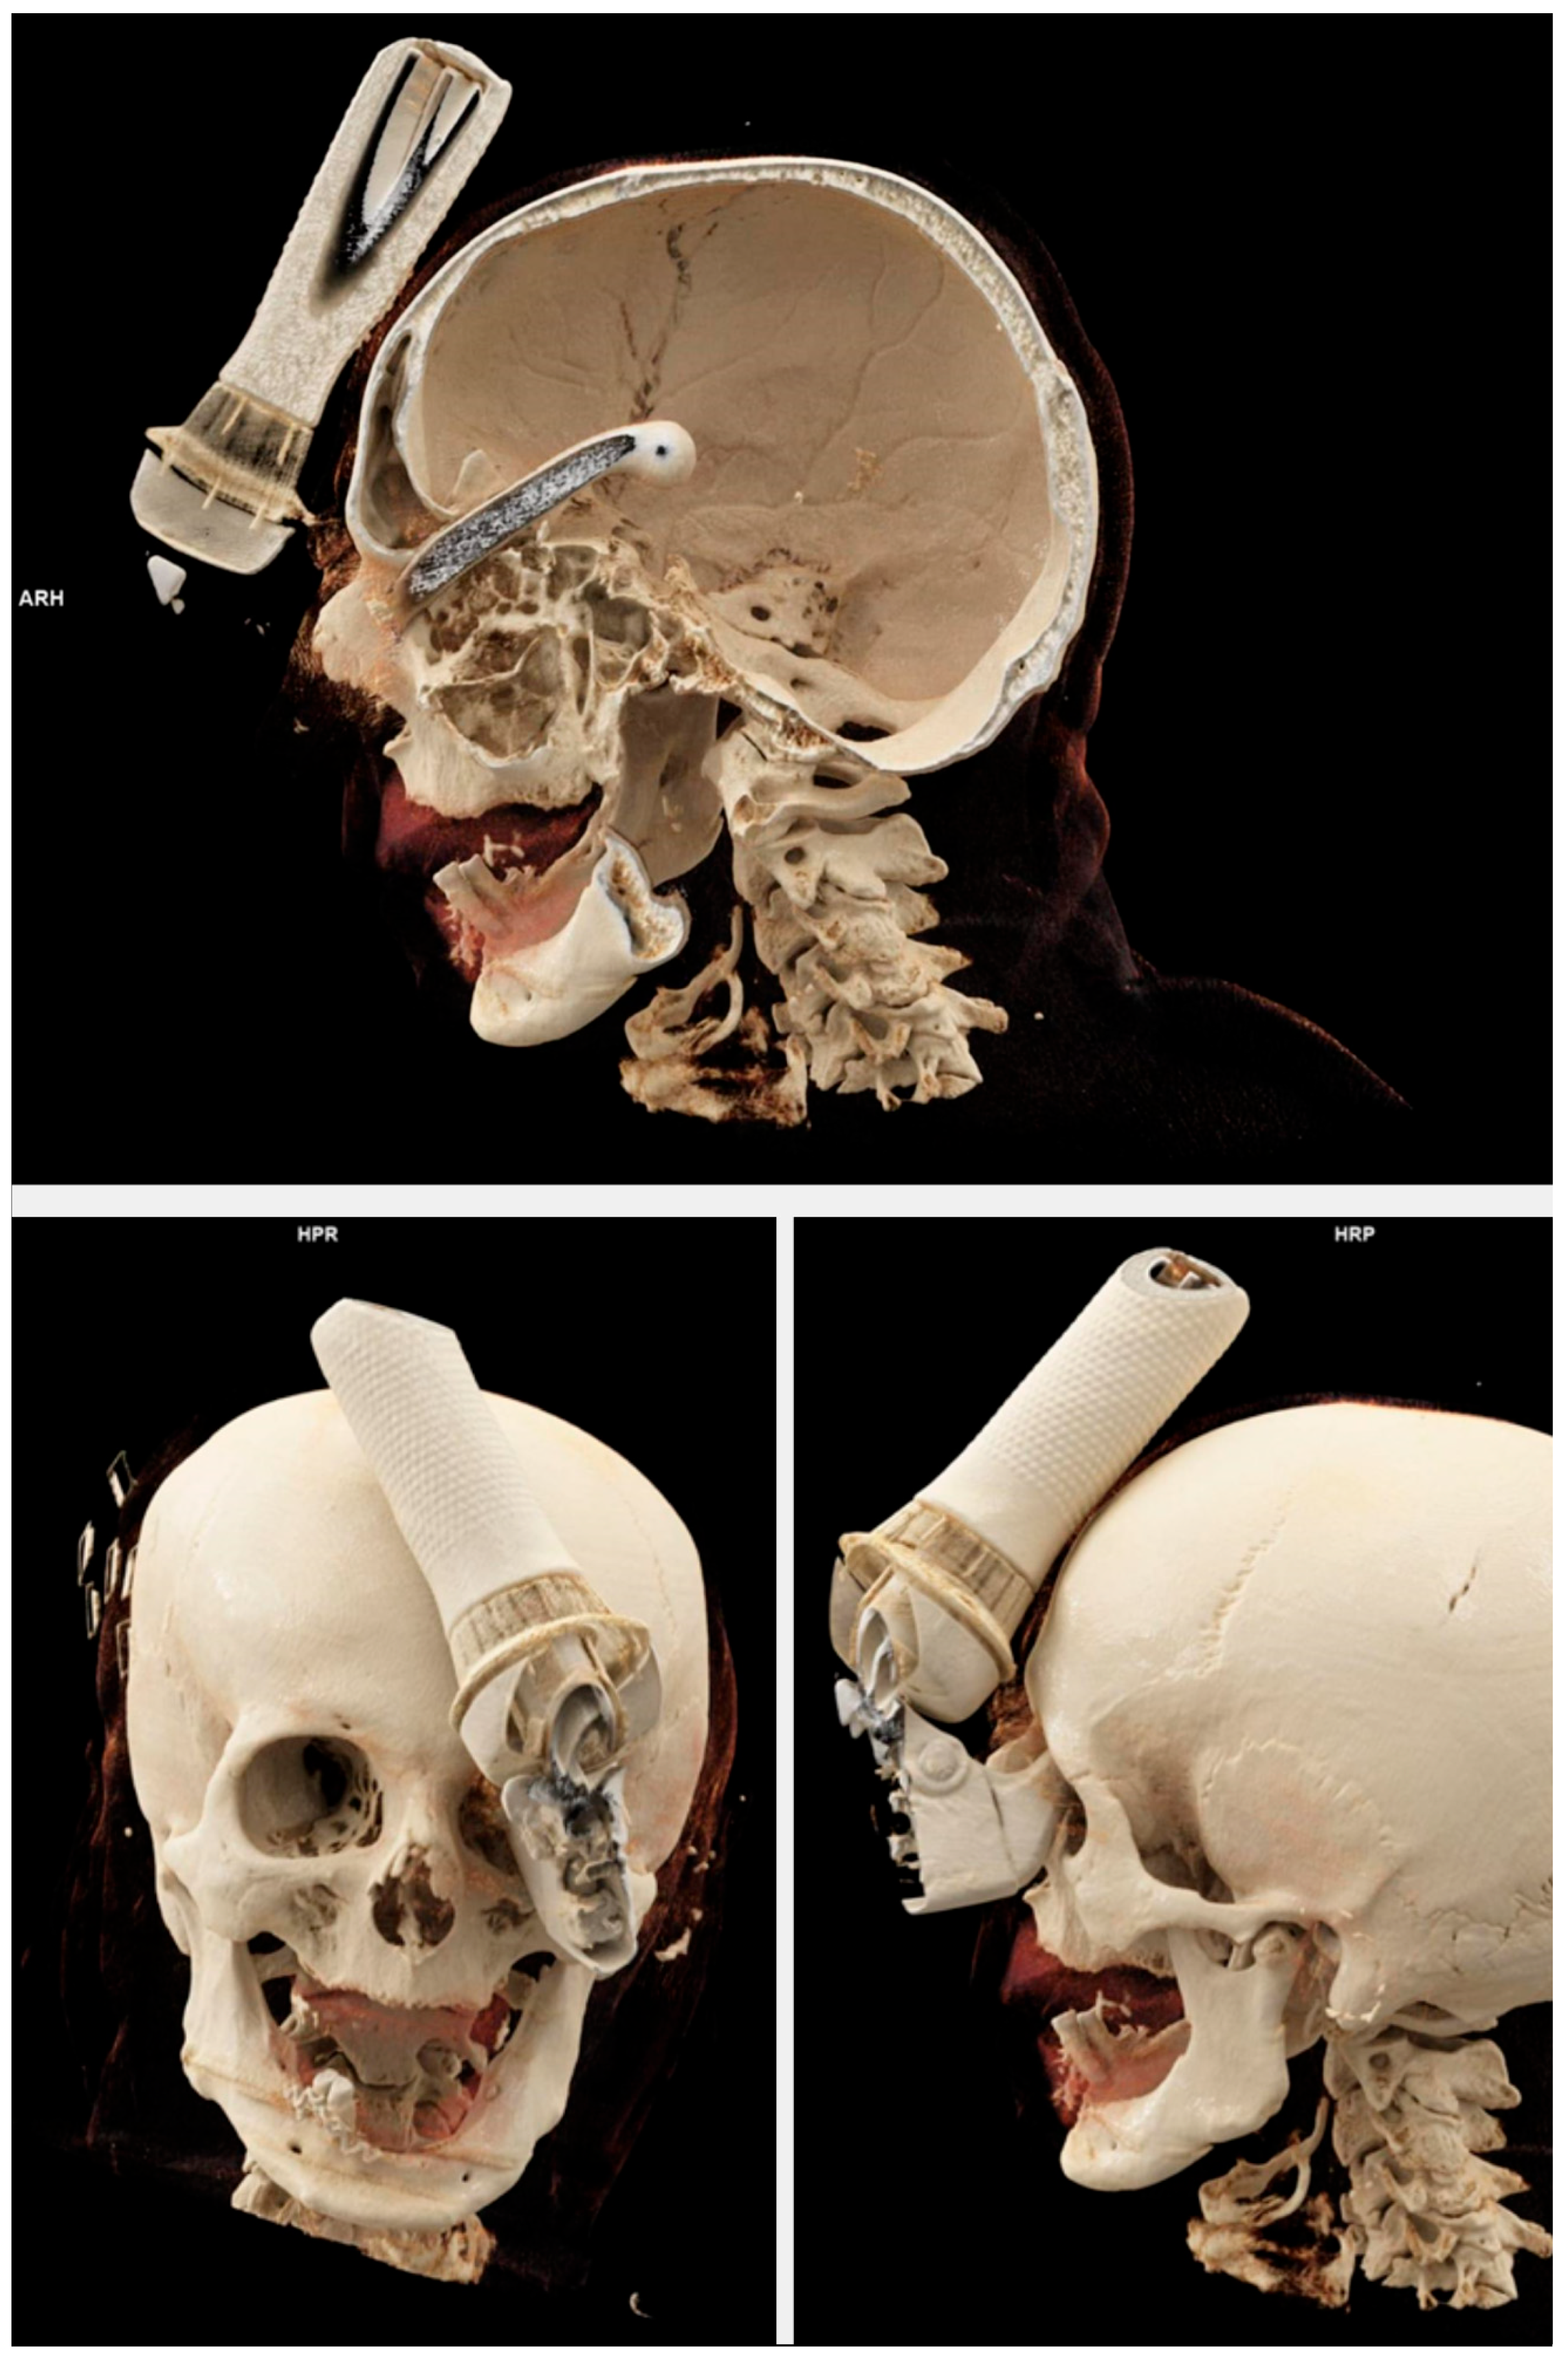

Figure 2. Three-dimensional bony reconstruction from CTA demonstrating a transorbital intracranial injury caused by an e-scooter brake handle.